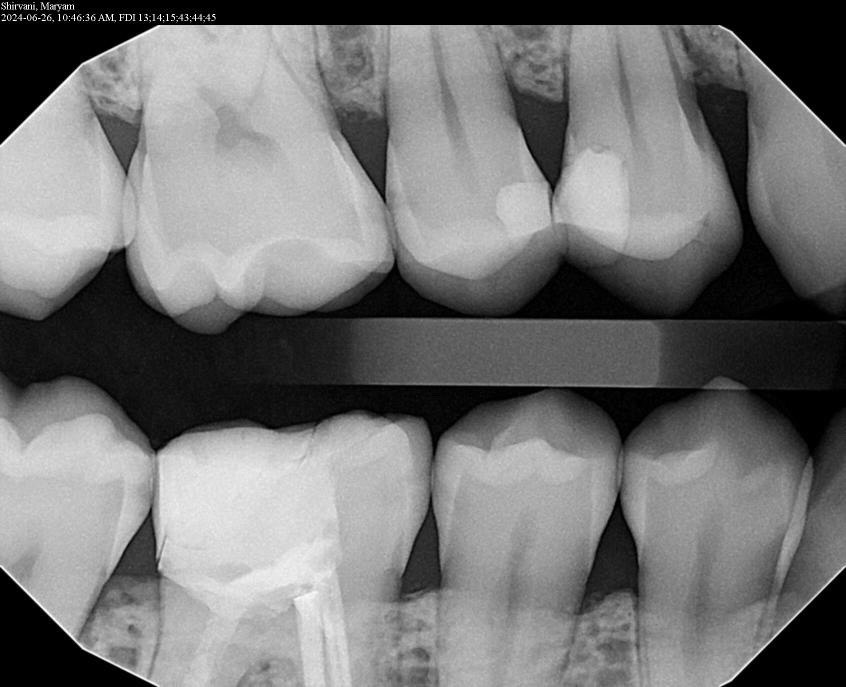

2. What surface require restoration?